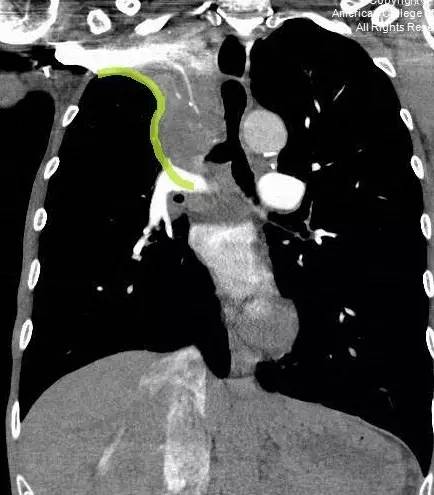

图 3. 冠状 CT 示「反 S」征(绿色箭头)。

「反 S」征指的是右肺上叶膨胀不全,水平裂向上移位,右肺门肿块共同形成胸片上反 S 形的凸出影。现结合 Zachary Laste 博士近日在 ACR 上发布的一例右上肺癌的病例对「反 S」征进行介绍。

「反 S」征是正位胸片上一个经典的影像学征象,最早由 Ross Golden 医生描述。S 征是由右肺上叶不张,水平裂向上中移位,中央型肿块向右肺门突出共同形成。正位胸片的典型表现包括水平裂向上凹陷,并向上内侧移位,以及肺门肿块形成的凸起。侧位胸片上,肺大间裂向前上移位是典型的表现。

当右肺上叶完全塌陷时,影像学上的表现为右侧帽装结构,或纵膈增宽。当看到向下突出的 S 征时,需要注意中央阻塞性肿物的可能性。有事这个征象也用来描述其他肺叶的膨胀不良。但是,最典型的还是右肺上叶的膨胀不良。